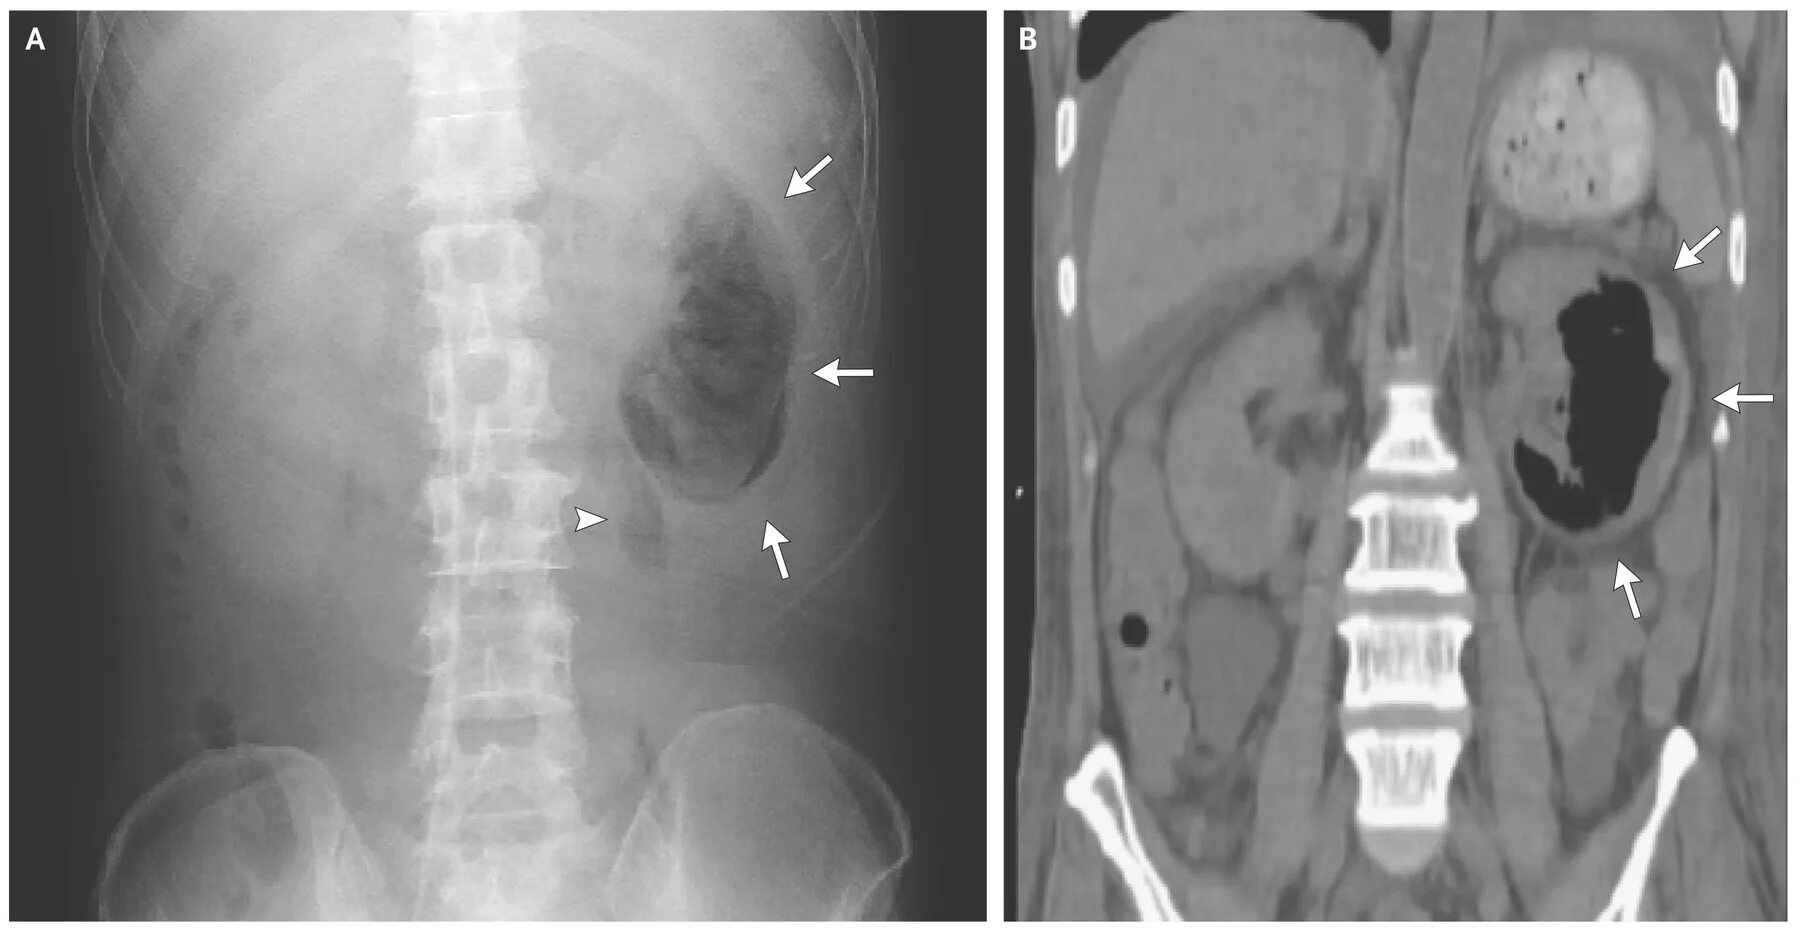

Пиелонефрит кт